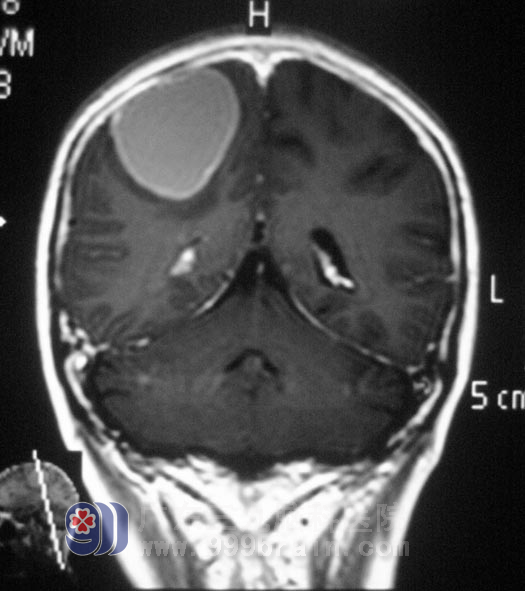

入院时伍女士呈深昏迷状,GCS评分6分,右侧瞳孔直径5mm,对光反射消失,左侧瞳孔直径4mm,对光反射迟钝,头颅MRI结果提示:右侧额叶占位,伴有出血,脑疝。综合神经外科鲁明主任亲自主刀急诊行右侧额叶占位切除术+去骨瓣减压术,见中央前回处黄色透明状病灶,显微镜下予以缜密切除。手术过程顺利,返回监护室予专科监护,双侧瞳孔等大等圆,对光反应灵敏,予抗炎、脱水、营养等对症治疗,术后第三天,伍女士神志清醒,对答切题,四肢活动基本正常。一周时间的治疗后,伍女士已经可以下床自行活动。术后经病理证实为:胶质细胞瘤WHO III级。已转放疗科行后续治疗。http://www.999brain.com/